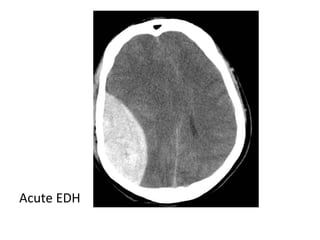

c) Hemorrhage :

-Frank hemorrhage into an arterial infarct

typically occurs a few days after the initial

stroke

-If there is hemorrhage within an infarct from

the outset , a venous stroke or arterial

embolus should be considered

-Hemorrhagic transformation with foci of hemorrhage

at the right post central gyrus

CT , Hemorrhagic evolution of initial ischemic infarction with

significant midline shift